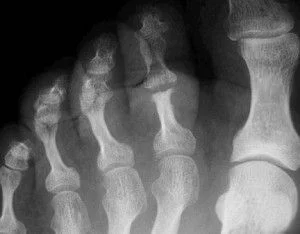

Pies

Destrucción extensa de la articulación interfalángica (IF) del 1º dedo.

La afectación de las articulaciones MTF es más común que en las MCF, y se acompaña de alteración de las IFD e IFP.

Es frecuente la erosión y proliferación ósea en el calcáneo con inflamación de la “inserción del tendón de Aquiles” se crean espolones irregulares y mal definidos que cursan con dolor en los talones al levantarse y dar los primeros pasos.